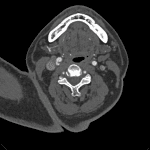

- Shelf-like smooth linear filling defect along the posterior wall of the right internal carotid artery just distal to the common carotid artery bifurcation

- Carotid webs characteristically arise along the posterior wall of the proximal cervical internal carotid artery and it is this location and their smooth, shelf-like contour that helps distinguish them from intraluminal thrombus or carotid dissection

- This characteristic appearance is often best appreciated on sagittal reformatted images